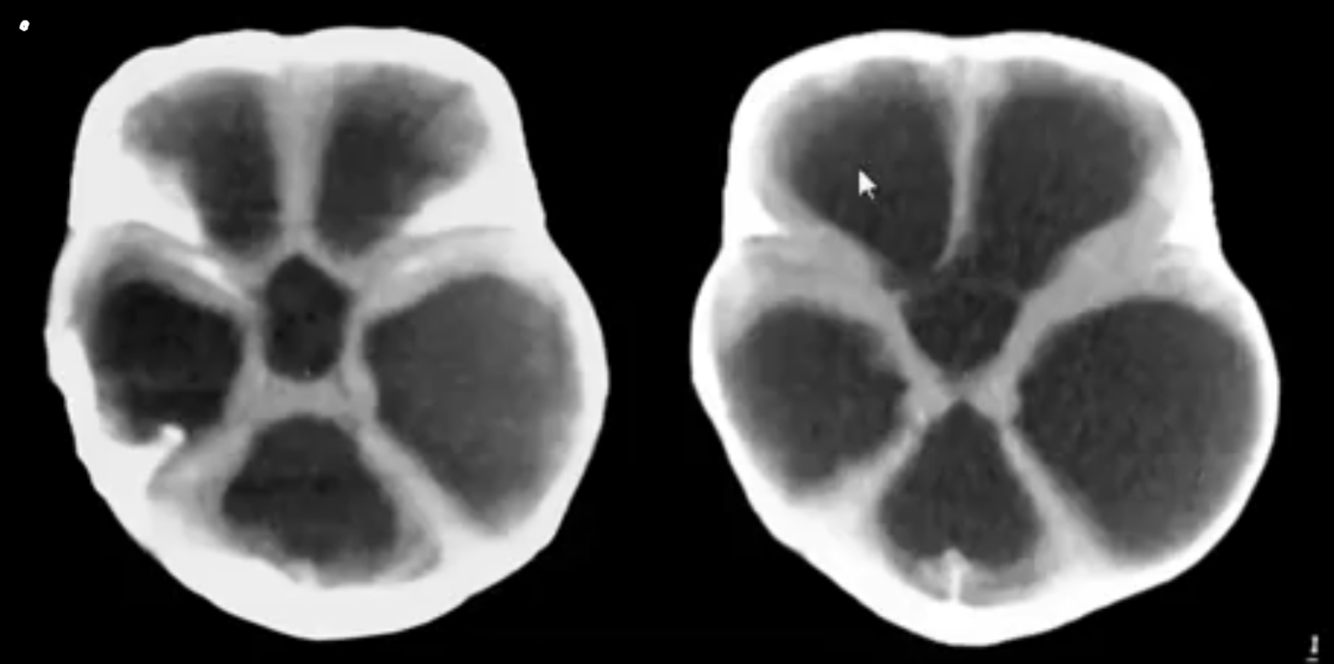

AQUEDUCTAL STENOSIS:

-congenital causes?

congenital causes:

aqueductal webs or diaphragms / gliosis